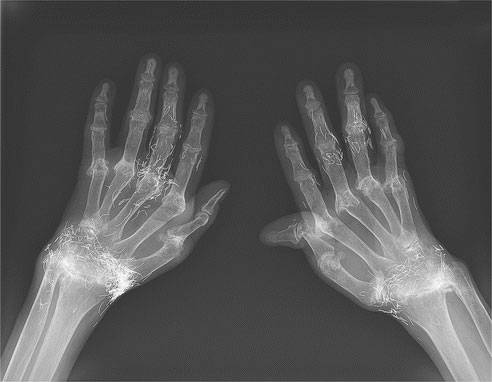

환자의 두 손을 보여주는 사진에는 실처럼 보이는 무언가가 몇십 개씩 박혀 있다. 금으로 된 바늘, 이른바 ‘금침’(金鍼)이다.

미국 뉴욕포스트 등 외신은 9일(현지시간) 이날 ‘뉴잉글랜드의학회지’(NEJM·New England Journal of Medicine) 웹사이트에 있는 ‘임상의학 이미지’(IMAGES IN CLINICAL MEDICINE) 부문에 위와 같은 희소 임상 사례가 실렸다고 보도했다.

이는 특히 수원 가톨릭대 성빈센트병원의 박경수 교수(류마티스내과 과장)와 주영빈 교수(임상조교수)가 보고한 국내 사례로, 지금까지 4만 8000회가 넘는 열람 횟수를 기록하며 이번 주 두 번째로 많이 본 게시물로 기록되고 있다.

보고서에 따르면, 환자는 58세 여성으로, 엑스레이 사진은 2014년 4월 촬영한 것이다. 환자는 18세 때부터 손발 관절이 아프기 시작해 10년 전 48세 때 류머티즘성 관절염을 진단받았다. 특히 이 환자는 진단을 받기 전까지 이부프로펜(진통제)으로 버티고 통증을 줄이려고 금침 치료를 받은 것으로 전해졌다.

금침 치료는 동양 의학 중에서도 전통적인 침술로 얇은 순금을 1㎝ 미만의 길이로 나눠 살균 처리한 뒤 통증 부위에 주입하는 방식인데, 그 효과는 과학적으로 입증되지 않았다.

이에 대해 박경수 교수는 “환자는 증세가 가벼웠던 초기에 항류머티즘성 약물을 사용한 적절한 치료를 받는 대신 침구 같은 전통의학에 의존했다”면서 “관절이 이렇게까지 변형한 원인은 류머티즘성 관절염과 관련이 있는 혈액 속 특정 단백질 상승 등 다른 위험 인자를 안고 있던 것과도 관계가 있다”고 설명했다.